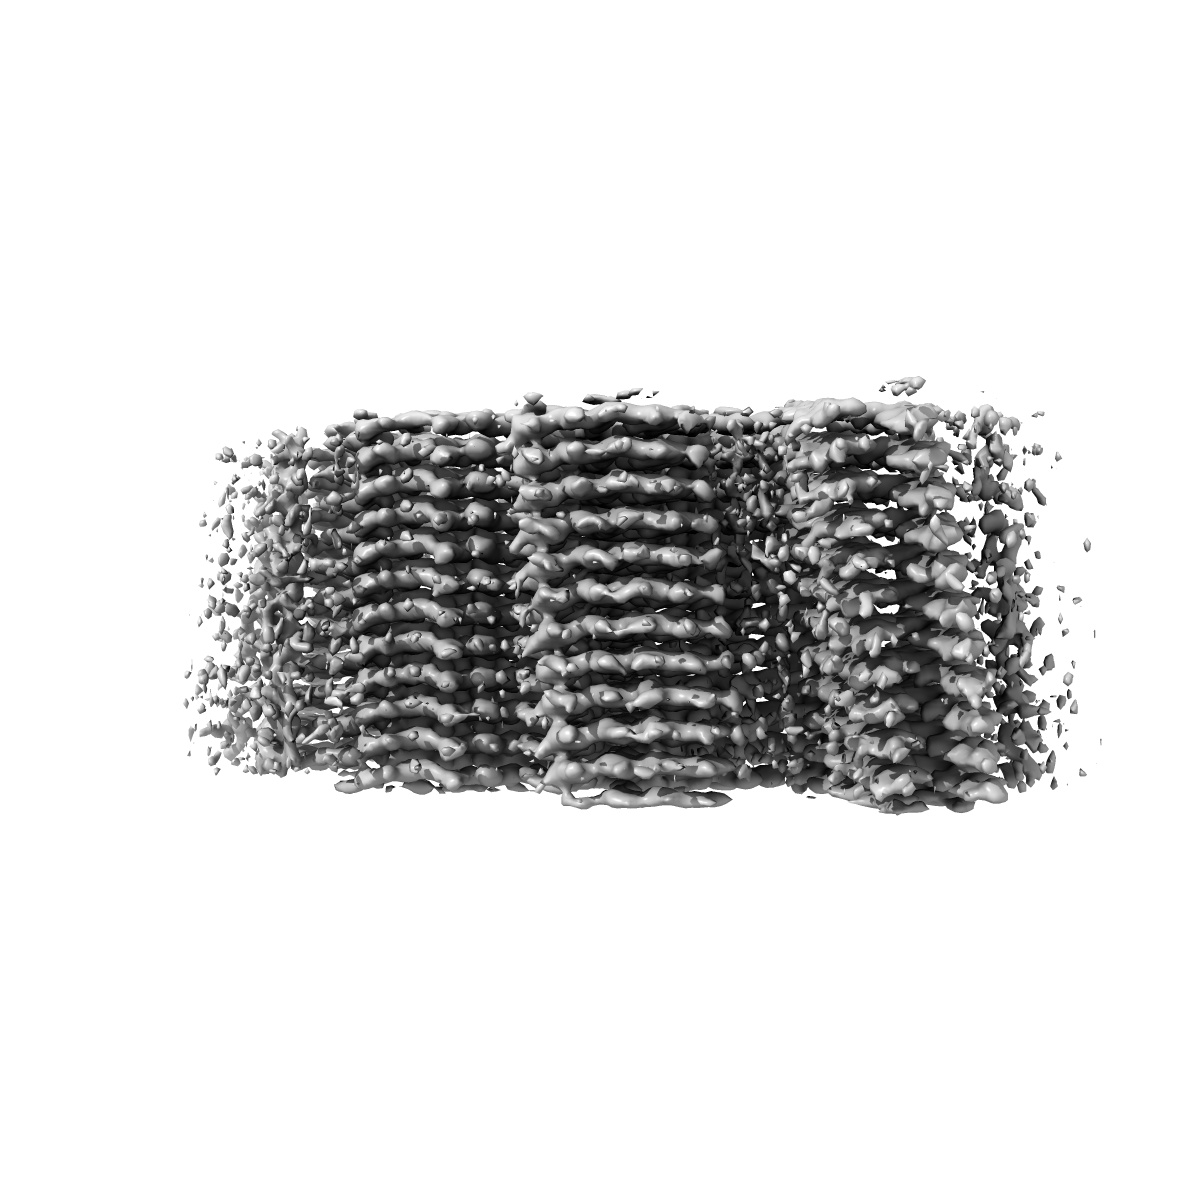

Paired Helical Filaments purified from Down Syndrome individual brain tissue applied to graphene oxide antibody affinity grids

Cryo-EM structures reveal tau filaments from Down syndrome adopt Alzheimer's disease fold.

Ghosh U, Tse E, Yang H , Shi M, Caro CD, Wang F, Merz GE, Prusiner SB, Southworth DR, Condello C

(2024) Acta Neuropathol , 12 , 94 - 94